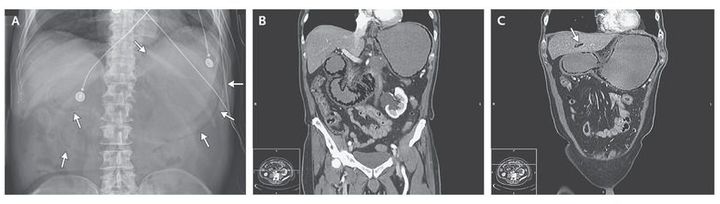

A 71-year-old man with advanced pancreatic carcinoma who was receiving neoadjuvant chemoradiation therapy presented with a 12-hour history of diffuse abdominal pain and vomiting with associated abdominal tenderness and rigidity. A plain abdominal film (Panel A) and computed tomographic scans (Panels B and C) revealed intestinal pneumatosis along the contour of the stomach and duodenum (Panel A, pylorus and duodenum, two arrows at lower left; lesser curvature of stomach, single arrow at top; greater curvature of stomach, three arrows at lower right), portal venous gas (Panel C, arrow), and adjacent bowel thickening. His poor oncologic prognosis, the extent of the bowel pneumatosis, and overall frailness led the patient to decline further intervention. He was transitioned to comfort care and died 48 hours after presentation. Intestinal pneumatosis may represent a finding incidental to life-threatening illness, as seen in this patient.